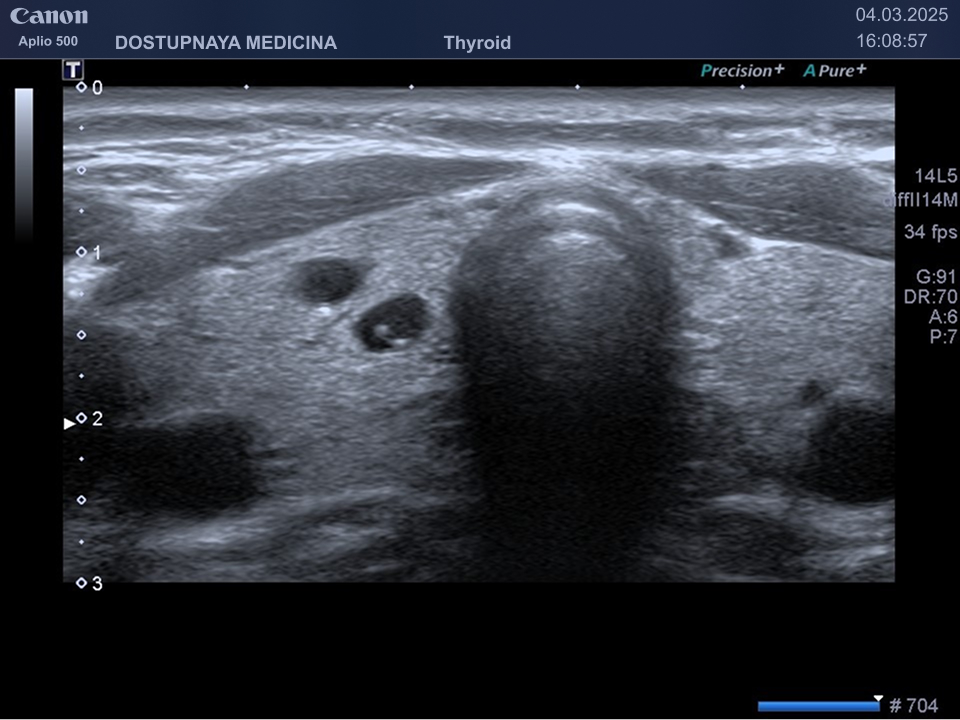

В ультразвуковой диагностике существует классификация образований щитовидной желзы по TIRADS, которая по различным критериям определяет степень онкоопастности того или ионого узла. При оценке учитывается эхоструткура образования ( кистозная, губчатая, солидная или солидно-кистозная), эхогенность ( анэхогенное, гиперэхогенное, гипоэхогенное), пространственная ориентация горизонтальная, вертикальная, неопределённая), контуры образования (ровные, дольчатые, зазубренные с острыми углами), наличие эхогенных включений( макрокальцинаты, микрокальцинаты, периферическая кольцевидная кальцификация). В зависимости от этих критериев выделяют различные категориии объёмных образований в щитовидной железе:

TIRADS 1 – доброкачественное образование.

TIRADS 2 – неподозрительное образование, требующие динамическое наблюдение.

TIRADS 3 – низко подозрительное образование, требующие динамическое наблюдение и тонкоигольной биопсии при размерах узла больше 2.5 см.

TIRADS 4 – умеренно подозрительное образование, требующие динамическое наблюдение и тонкоигольной биопсии при размерах узла больше 1.5 см.

TIRADS 5 – высоко подозрительное образование, требующие динамическое наблюдение и тонкоигольной биопсии при размерах узла больше 1 см.